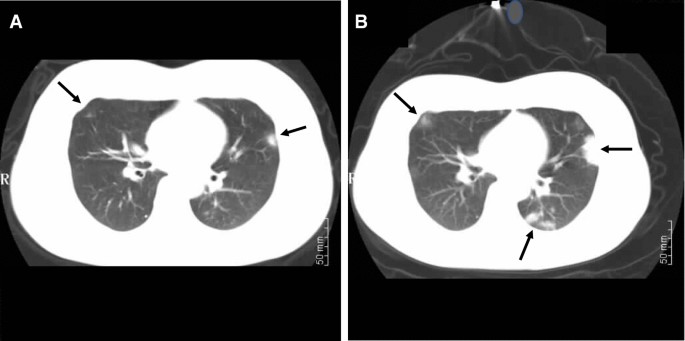

Chest Computed Tomography Images Of Early Coronavirus Disease Covid 19 Springerlink

link.springer.com